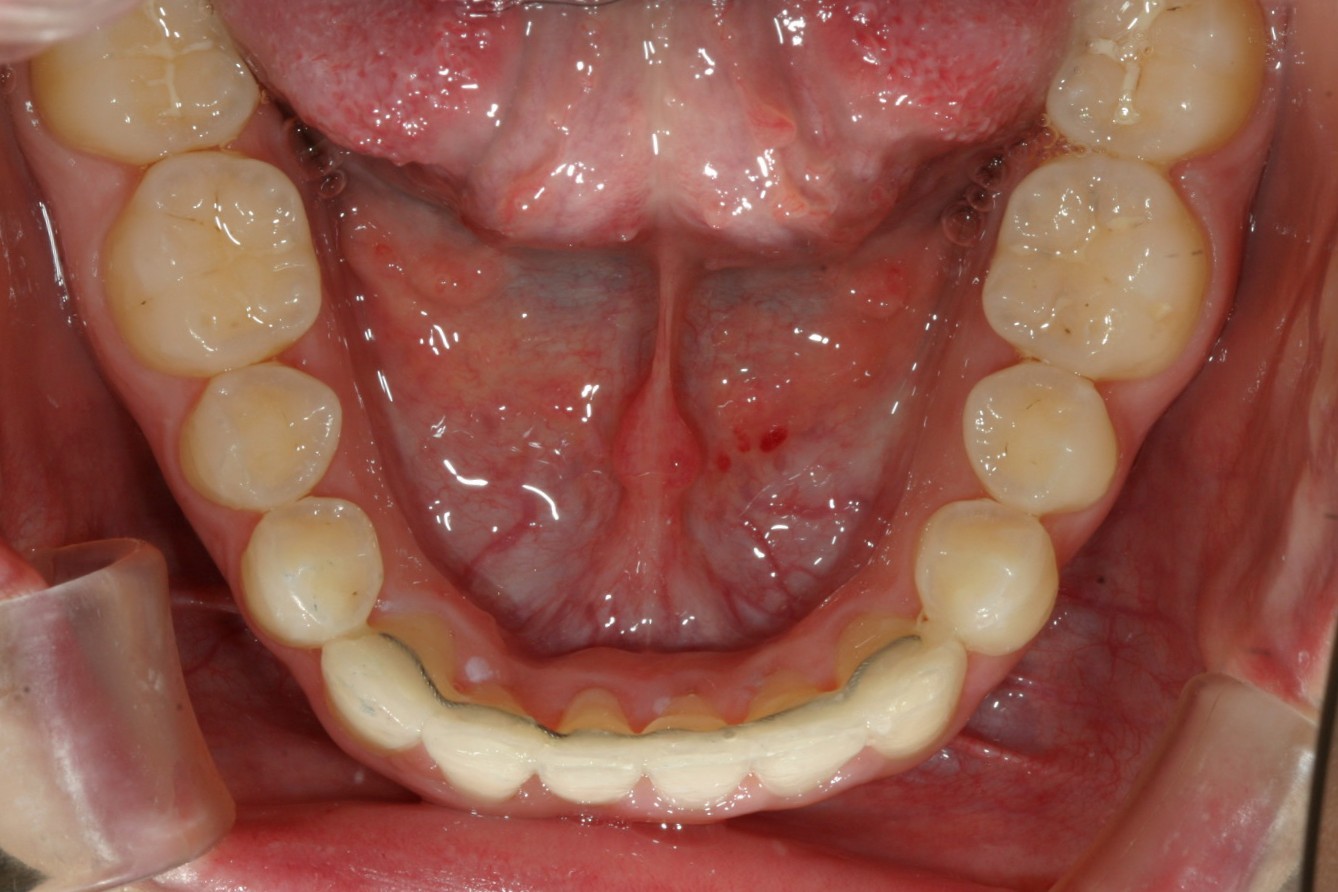

下顎も綺麗に改善してます。

術前と比べると少しオーバージェットが増しました。

今回のケースも叢生ではよくあるケースで歯列弓が全体的に狭くなり結局そのしわ寄せが前歯に来て叢生になっています。

いつも通りアーチの拡大とIPR(歯と歯の間を少し削る)によりガタガタを取り又出っ歯を改善します。

これだけガタついている歯がここまで綺麗になれば他人からの第一印象もかなり変わると思います。